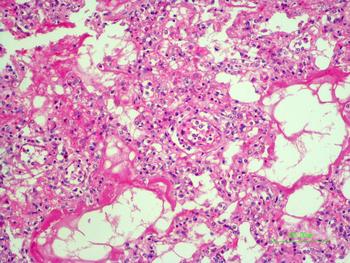

The autopsy revealed petechiae and generalised oedema (Fig. 1), congestion and focal haemorrhage in multiple organs associated with generalised vasculopathy of small-medium vessels with partial fibrin microthrombi formation, pericardial, pleural and peritoneal effusion, and interstitial pneumonitis with diffuse alveolar damage (Fig. 2). Additionally, the patient had foci of endo-myocarditis, acute renal tubular necrosis and chronic hepatitis.

Fig. 2. Interstitial pneumonitis and diffuse alveolar damage (HE 100×).